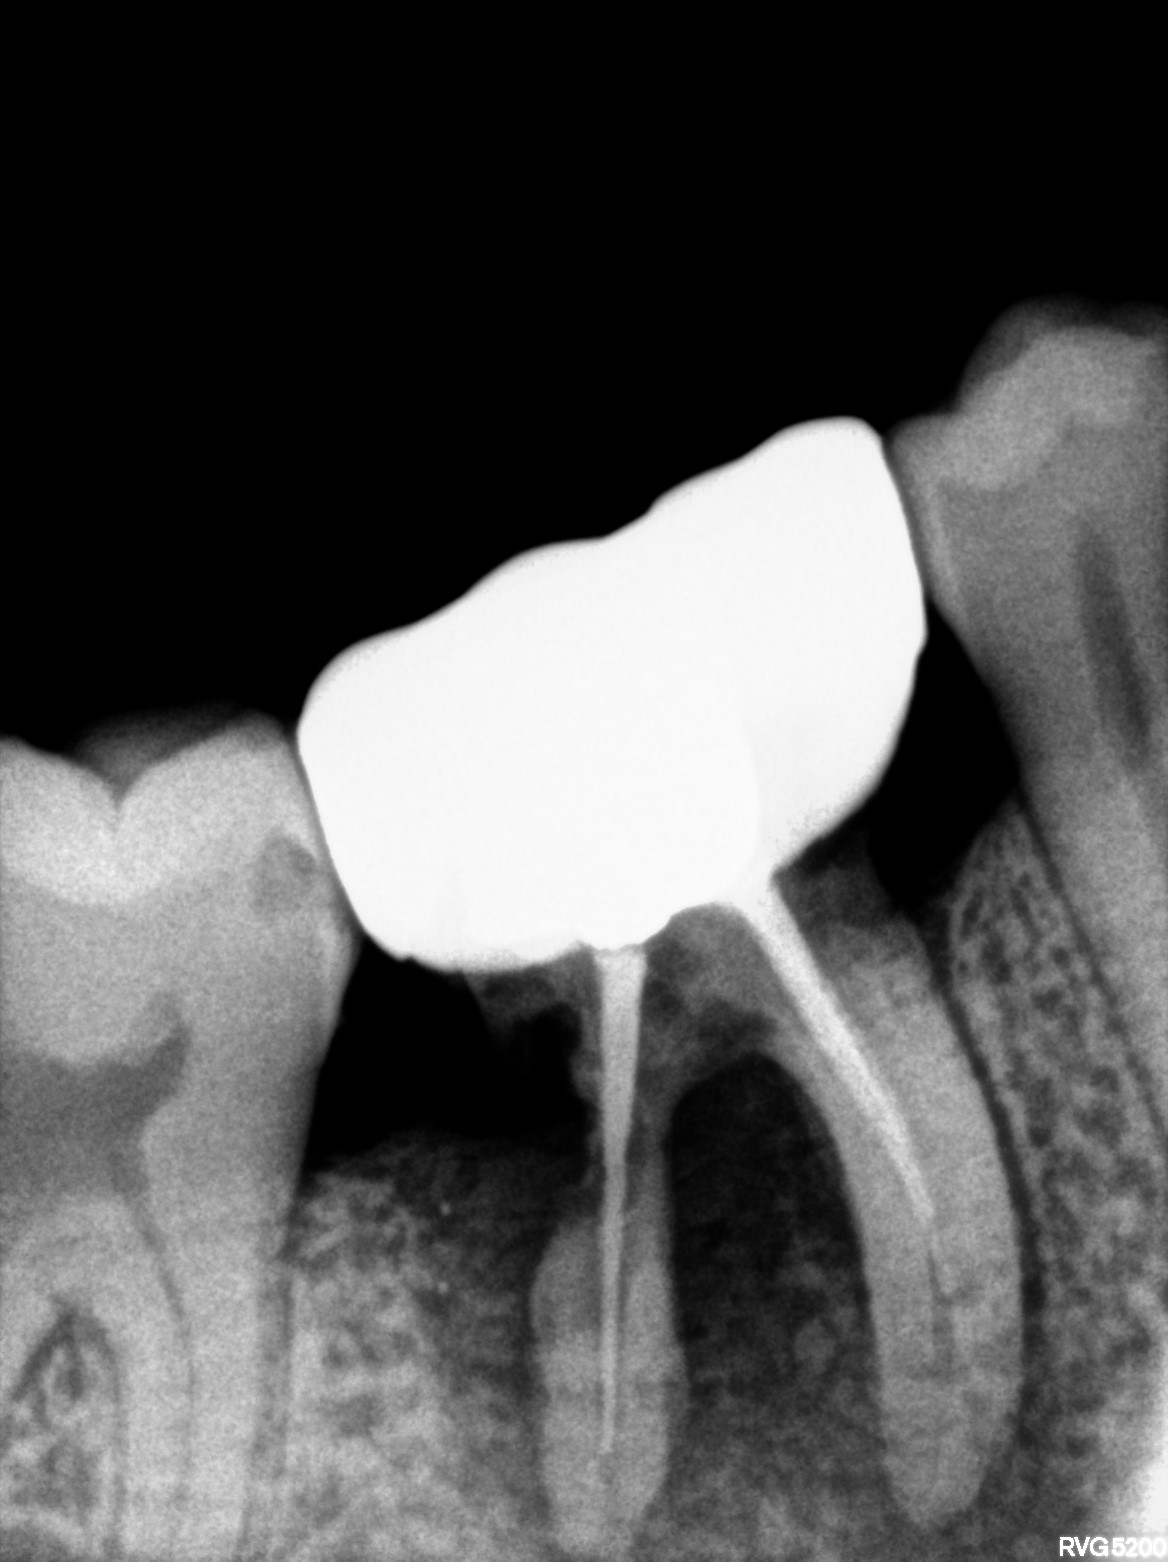

Dental Radiographs FHIR: DocumentReference · LOINC 24641-7

R58.jpg

24641-7